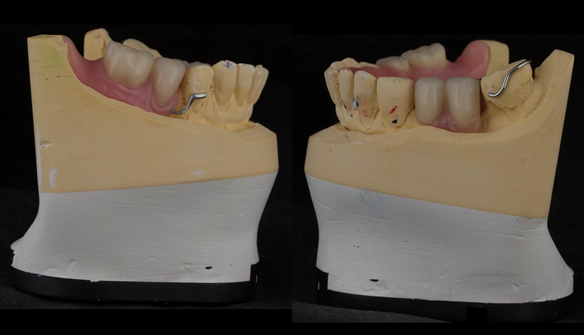

This newsletter describes in step by step detail Angela's transition through immediate partial dentures to crown supported definitive metal based dentures.

The clinical situation and treatment process is shown in detail below with photographs. I (Finlay Sutton) provided the clinical work and Rowan Garstang provided the technical work.